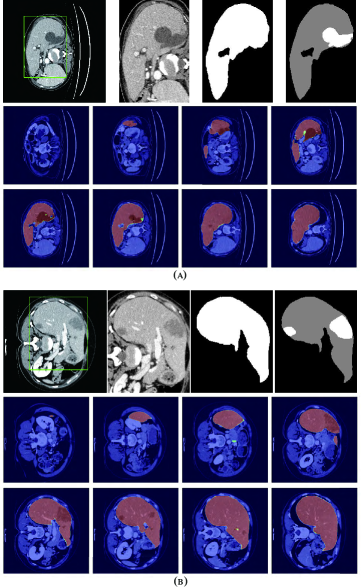

Refer to caption

Figure 8: Liver segmentation results based on RA-UNet-\@slowromancapii@. (a) is from the LiTS validation dataset and (b) is from the 3DIRCADb dataset. From left to right, the first row of each subplot shows the liver in the green boundary box, magnified liver region, the liver segmentation results, and the corresponding ground truth. The second and the third rows show the probability heat map of liver segmentation results. The darker the color is, the higher the possibility of the liver region is. Note that the ground truth contains liver in gray and tumor in white.